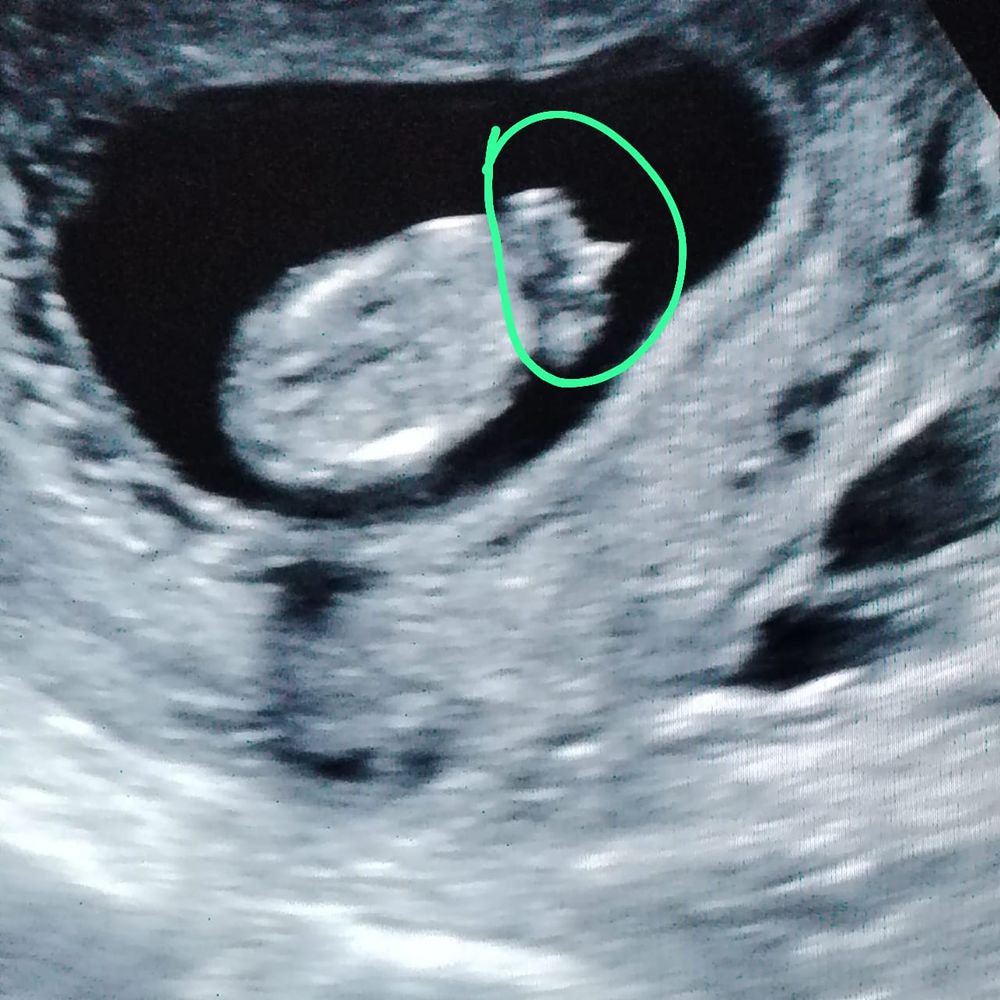

Илона, скажите пожалуйста как сюда его загрузить?)) Изображение Изображение Изображение

Ирина Качанова, я бы больше склонялась что это клитор, у них торчит на этом сроке..

Евгения , вот такие только) вот обвели и говорят мальчик)

16.12.2024

Ирина Качанова, неудачные фото узи. Жаль что нет других

Ирина Качанова, если бы сбоку фото было еще можно было бы предположить( тут будто сверху лялю сфоткали